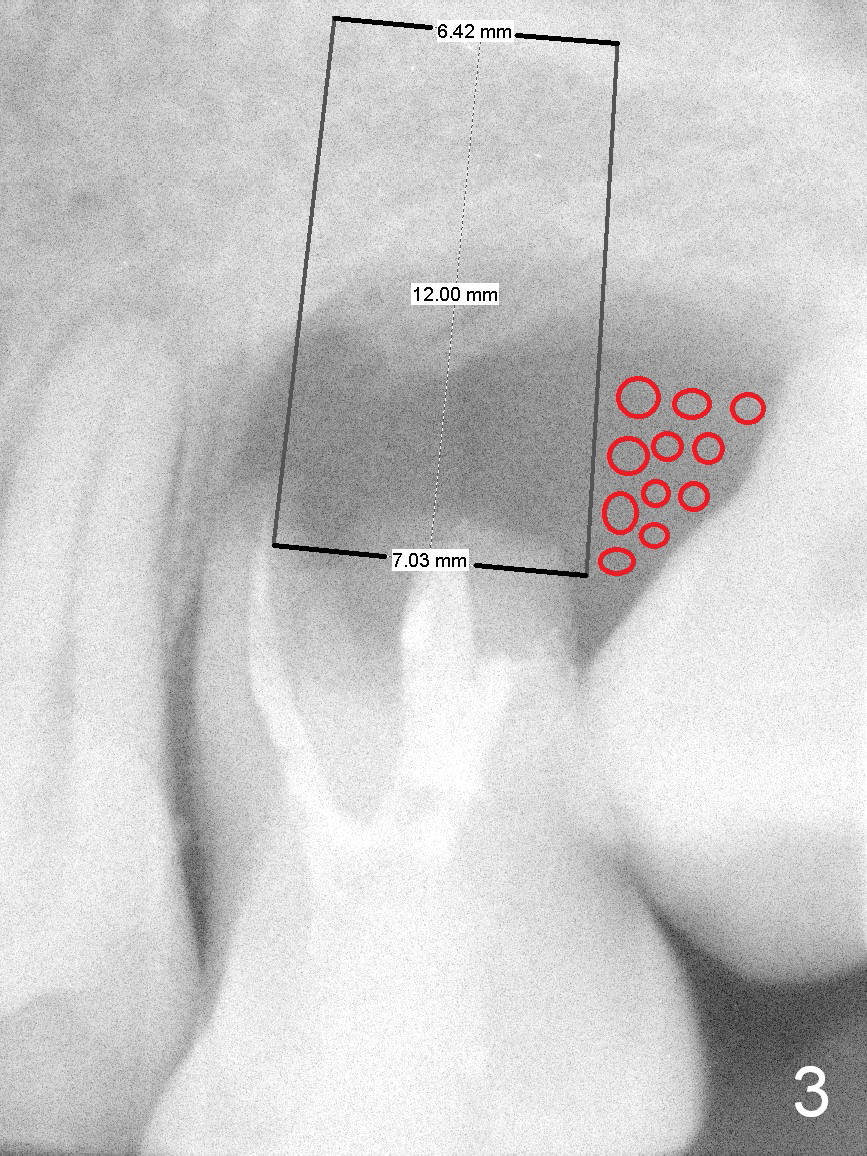

A 42-year-old man (XK) has perio-endo disease at the tooth #14.  After root canal therapy (Fig.1), the tooth remains nonsalvageable.  The bone loss is extensive (Fig.1 *) and uneven (more bone mesially than distally) after extraction (2% Xylocaine/1:50,000 Epinephrine).  A bone-level implant is placed in an ideal depth (Fig.3 UF; Fig.4 SM), irrelevant of the gingival margin, first.   Place bone graft distally (Fig.3 red circles) before choosing a proper abutment.  For example, there is plenty of combination to choose cuff and abutment lengths for a SM or UF implant (Fig.4).